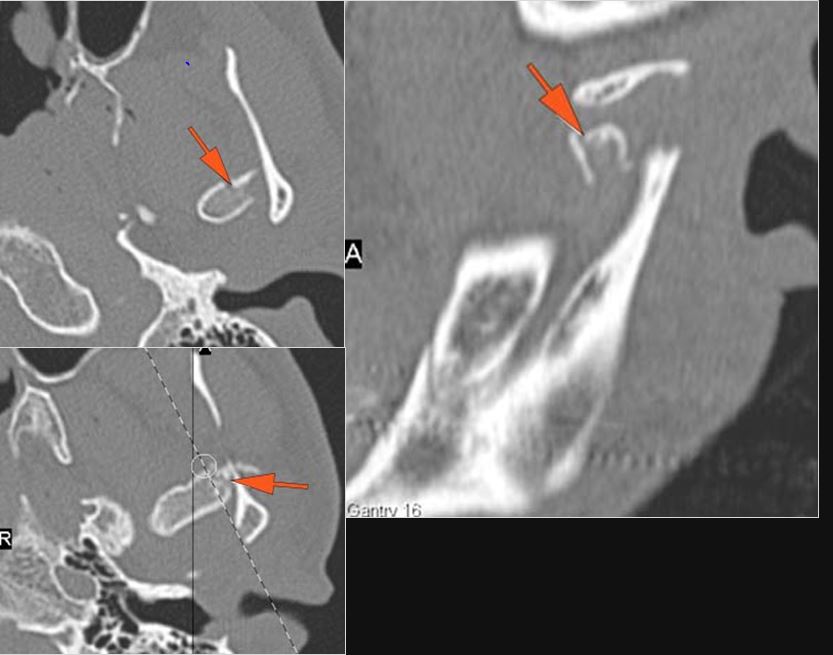

There is condylar fracture either within or outside of the joint capsule, or with or without involvement of the articular surface of the condylar head.

There is evidence of radiodense intra-articular osteochondral fragments.

There is bony injury or displacement of the external auditory canal and/or other evidence of temporal bone injury.